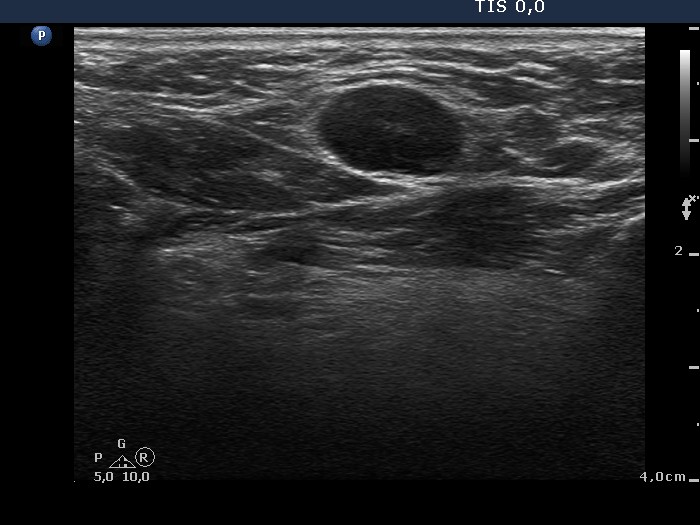

Lymph nodes - case 80 (ultrasonographic picture 6)

Submental region, longitudinal scan.